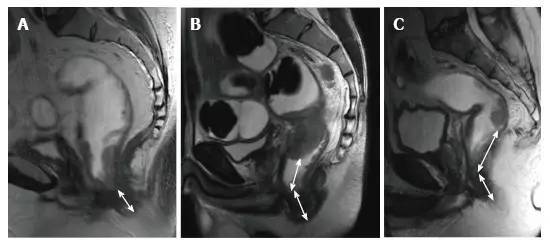

图 18. DWI 对放化疗后为 ypT3 的肿瘤重新分期。A. T2 加权轴位显示治疗后半圆形浸润肿瘤,与残留的 T3 肿瘤相符(箭头);B. 治疗后 DWI;C. ADC,图像分别对应肿瘤的高低信号强度,治疗前后 ADC 值分别为 0.68-0.72 和 1.22-1.44×10-3 mm²/s,治疗后 ADC 值增加与治疗反应相符。

图片

图 19. DWI 对放化疗后 ypT0 直肠肿瘤重新分期。A. 治疗后 T2 加权轴位图像显示,先前直肠肿瘤区域的低信号强度纤维化厚壁(箭头),难以确定该区域是否含有肿瘤细胞还是完全缓解;B. 在治疗后 DW 图像(B-800)中,在以前的肿瘤区域(箭头)没有弥散信号,与完全缓解相符。在这种情况下,DWI 正确区分肿瘤与纤维化;C. ADC 图像显示治疗后平均 ADC 增加(0.70 × 10-3 mm²/s 对比 1.40 × 10-3 mm²/s)与治疗反应相符,但不能预测完全缓解。